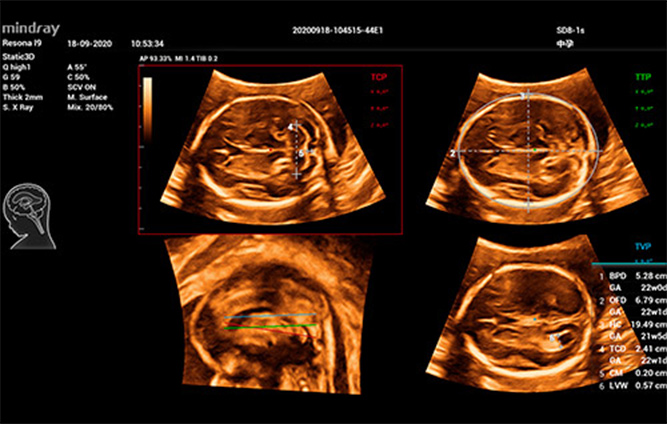

Mindray, kullan?c? ba??ml?l???n? azaltmak ve te?his verimlili?ini art?rmak i?in, fetal beyin, yÞz, omurga ve uzun kemikler gibi tipik 3B ultrason muayenelerine ili?kin tipik klinik senaryolar i?in, tek bir t?klamayla otomatik sahne tan?mlamas?, otomatik g?rÞntÞleme optimizasyonu, otomatik dÞzlem al?m? ve otomatik ?l?Þm yap?lmas?n? sa?layan, klinik senaryo tabanl? yenilik?i bir 3B/4B etkile?imi geli?tirdi. ProsedÞr boyunca otomatik i? ak???n? ger?ek anlamda uygular ve daha iyi hasta bak?m? sa?lamak i?in gÞ?lÞ te?his ?zgÞveni sunar.

Smart Planes CNS

Ak?ll? ICV: Otomatik intrakraniyal hacim hesaplamas?

Smart Face

Fetal omurgan?n 3B/4B ultrason g?rÞntÞleri